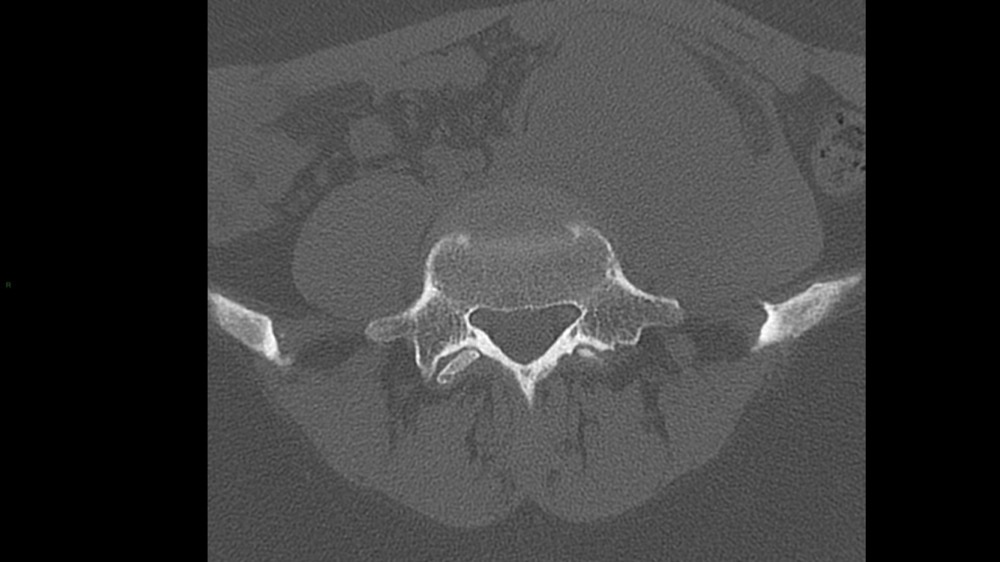

Bone Club

Cédric Sepulveda 19/01/2022